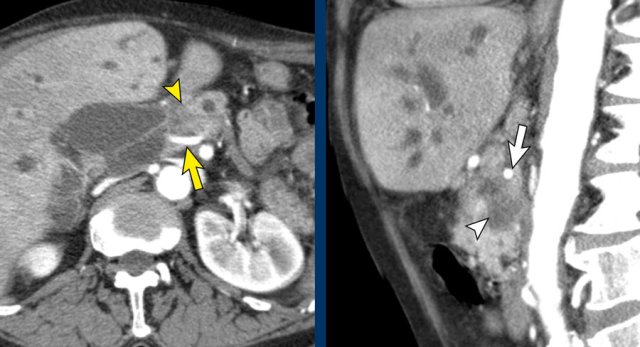

The use of multiplanar reformations improves overall CT performance as seen in this case.

A coronal reformat shows a small tumor in the pancreatic head (arrowheads) with obstruction of the common bile duct.

There seems to be just limited contact with the portal vein (arrow).

Continue with the next images.

A multiplanar reformat perpendicular to the portal vein shows that there is more extensive contact with the portal vein, 90 – 180 degrees (arrow).

Without contour irregularity this is classified as borderline resectable according to the DPCG criteria but resectable according to the NCCN criteria.

Resection without venous reconstruction proved to be R1, meaning presence of microscopic tumor invasion of the resection margin.

The axial CT shows a accessory right hepatic artery (yellow arrow) running in close proximity to a hypodense mass in the pancreatic head (arrowhead).

The vascular involvement is better appreciated on the sagittal reconstruction. There is 90 – 180° abutment of the replaced right hepatic artery (white arrow) by a pancreatic head adenocarcinoma (white arrowhead).

The native left hepatic artery is seen in a more anterior course, the portal vein in between.

The operation was a R1-resection.